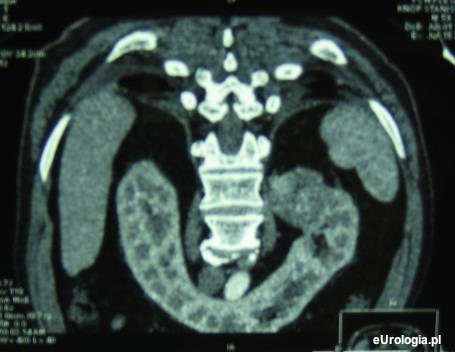

Fot. Obraz tomograficzny nerki podkowiastej z guzem górnego bieguna nerki lewej.